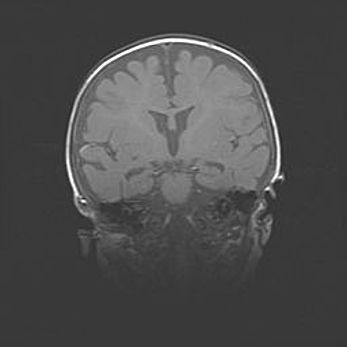

Церебральная ишемия II.

Возраст: 5 дней

Вес: 3400 г

Пол: женский

Окружность головы: 35 см

Срок гестации: 39 недель

Церебральная ишемия – это заболевание, характеризующееся недостаточностью (гипоксией) либо полным прекращением (аноксией) снабжения мозга кислородом по причине закупорки одного или нескольких сосудов. Это приводит к  что метаболическим расстройствам различной степени тяжести в тканях головного мозга, развитию коагуляционных некрозов и гибели нейронов.